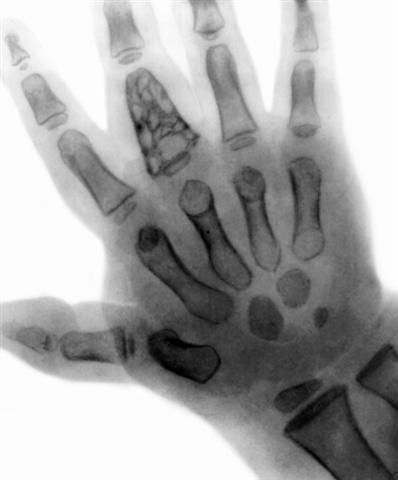

Рис. 6. Рентгенограмма левой кисти в переднезадней проекции при туберкулезе диафиза проксимальной фаланги III пальца (spina ventosa): диафиз проксимальной фаланги III пальца резко расширен, слой компактного костного вещества истончен, в диафизе и метафизе определяется обширное просветление (деструкция) с участками затенения, секвестры, мягкие ткани в зоне поражения уплотнены. |